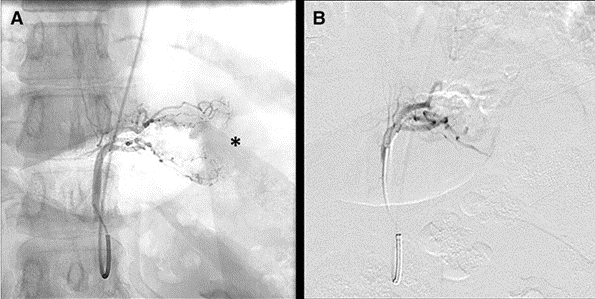

The procedure entailed angiographic studies of left gastric artery (LGA), gastroduodenal and splenic arteries followed by targeted embolization of the LGA, the dominant artery feeding the fundus, and in certain cases, additional feeding vessels (accessory left gastric artery, gastroepiploic artery, and short gastric artery ) with Embospheres 300-500 μm.

Fig. 1 A Left gastric digital arteriogram (non-subtracted) in the supine position from the left radial approach showing arterial branches to the gastric fundus (*) and proximal body. B Left gastric digital subtraction arteriogram after embolization with Embospheres showing occlusion of the distal branches of the left gastric artery